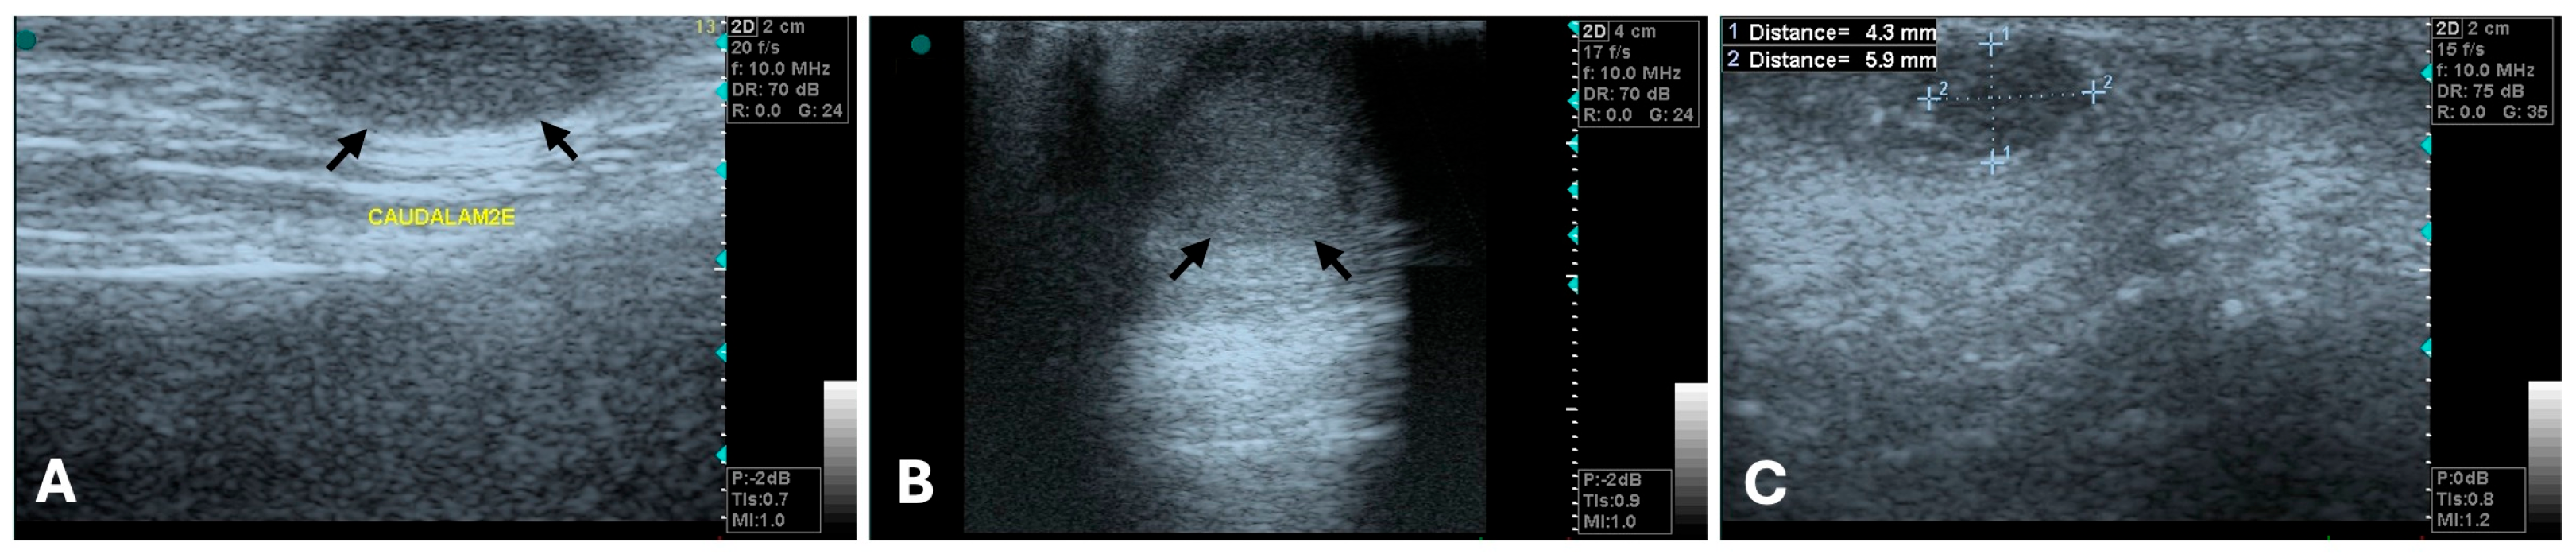

3.1. Ultrasonography

- Vannozzi, I.; Tesi, M.; Zangheri, M.; Innocenti, V.M.; Rota, A.; Citi, S.; Poli, A. B-Mode Ultrasound Examination of Canine Mammary Gland Neoplastic Lesions of Small Size (Diameter < 2 cm). Vet. Res. Commun. 2018, 42, 137–143. [Google Scholar] [CrossRef]

| Margins/Contour | Usually well-defined, smooth, regular [40,75,76] | Usually ill-defined, irregular, spiculated [76,78,82] | Non-defined margins were not reliable in differentiating benign/malignant lesions [78] |

| Shape | Round to oval [76,78] | Irregular, microlobulated [78] | Malignant tumors often distort surrounding tissue |

| Echotexture Echogenicity (US) | Homogeneous, hypoechoic or isoechoic [40,75,78] | Heterogeneous, mixed echogenicity [75,76,78] | Heterogenicity due to edema, hemorrhage, calcification, cystic/necrotic areas [75] |

| Posterior acoustic features (US) | Shadowing or enhancement more likely [78,80] | Shadowing [40] or enhancement more likely [75,76,79] | Features not consensual [78,81] |